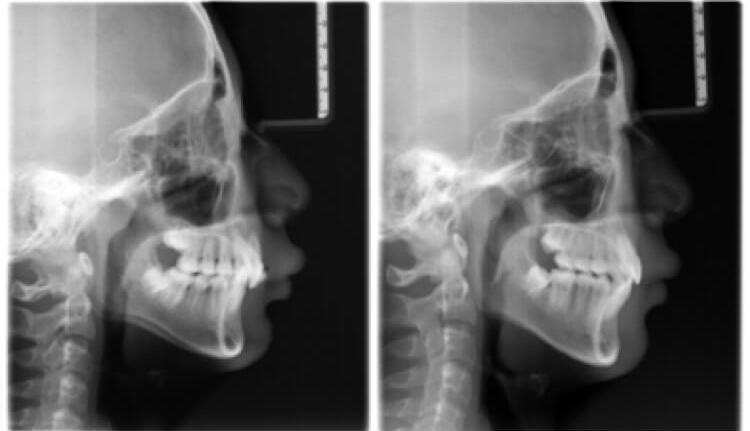

医学类型:深覆合, 牙列拥挤

矫正方法:固定矫正, 平导

治疗周期:18个月

这个男孩是15岁来我这矫正的,主诉是上嘴唇突出。

其实他是牙齿拥挤,伴有严重的深覆合,所以看上去下巴后缩,面下三分之一短,显得上嘴唇很突出。

我采用了不拔牙矫治,平导打开咬合,总疗程18个月后,男孩收获了帅气阳光的面容。